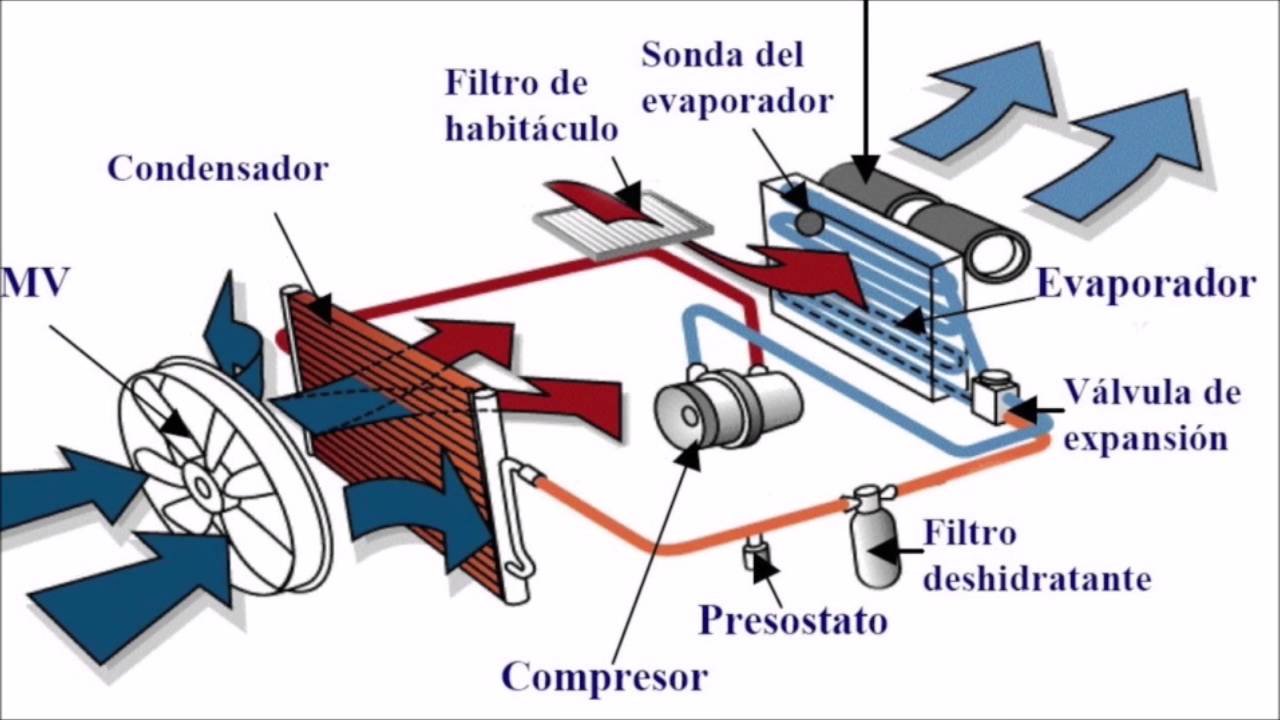

SISTEMA DEL AIRE ACONDICIONADO

AIRE ACONDICIONADO